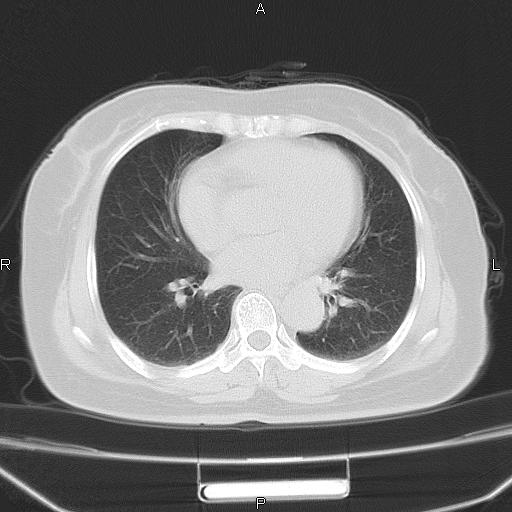

胸腺瘤

女、63Y 双眼睑下垂,早轻晚重。 胸腺瘤???

结果胸腺瘤